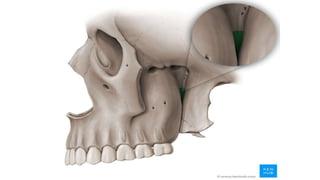

Inferior orbital fissure

Content

• Inferior ophthalmic veins

infraorbital artery

infraorbital vein,

• Tributary of pterygoid plexus

• Zygomatic nerve and infraorbital

nerve of maxillary nerve (V2)

• Orbital branches

of pterygopalatine ganglion